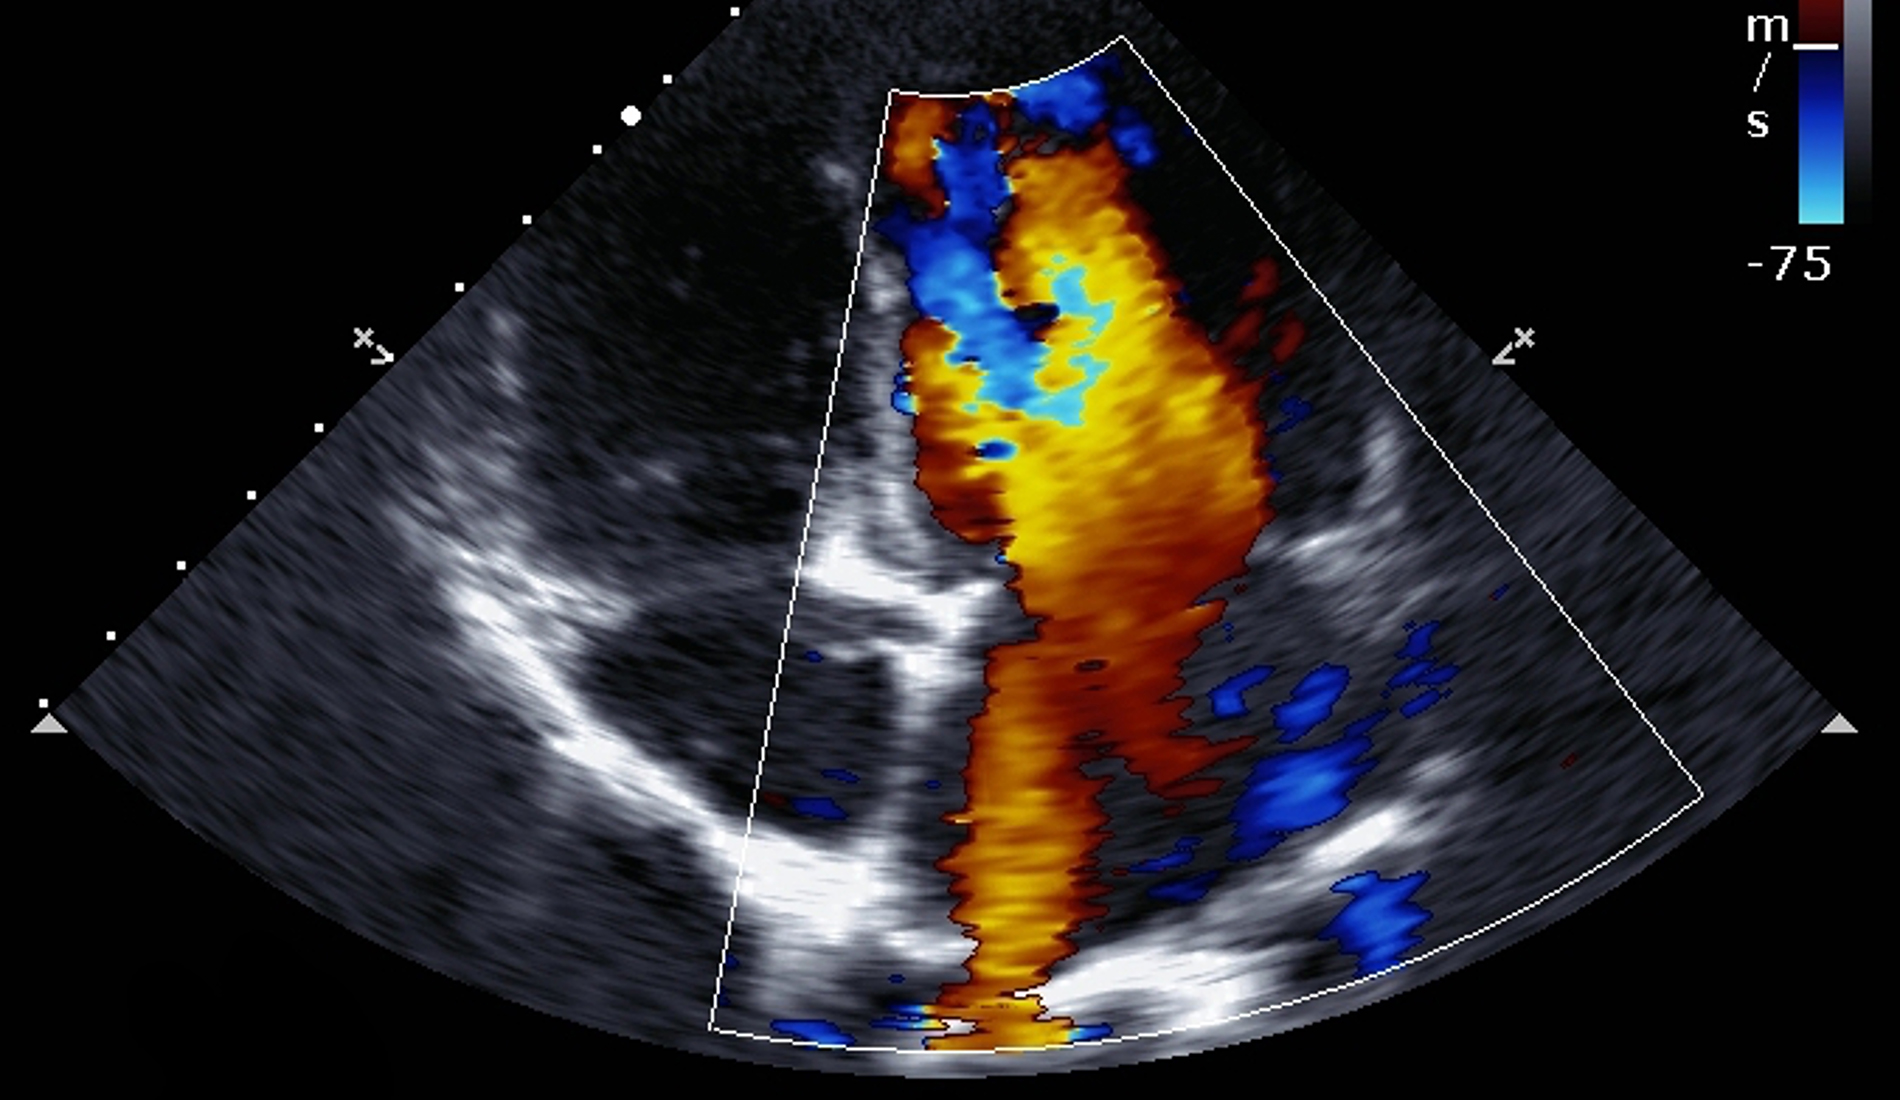

Contributors: Preeya Prakash MD, Adam Greenhaw PharmD, Travis Barlock MD, and Jeffrey Olson MS4 In this episode, cardiologist Preeya Prakash and medical student Jeffrey Olson listen in as two cases are presented from EMM's recent event, Tox Talk 2025. Talk 1- Digoxin Overdose Dr. Adam Greenhaw presents a case of a Digoxin overdose along with many pearls. During the studio listen in, Dr. Prakash helps to answer the questions of: How does digoxin work? Why might a patient still be on digoxin in 2025? What are the EKG findings of digoxin toxicity? Is there any utility in atropine for bradycardia caused by digoxin? Should you use calcium to treat hyperkalemia in the setting of a digoxin overdose? If/when might a cardiologist get involved in a patient with a digoxin overdose? Talk 2- Propranolol Overdose Dr. Travis Barlock presents a case of a beta blocker overdose as well as many associated pearls. During our studio listen in, Dr. Prakash helps to answer the questions of: What are the different beta blockers and how do they work? If you are worried about a propranolol overdose, what medications do you want on hand? What POCUS cardiac view can give you the most information for different scenarios? Why or why not might transcutaneous or intravenous pacing be a good idea for a beta blocker overdose? If/when might you want a cardiologist to get involved in a patient with a beta blocker overdose? References Alahmed AA, Lauffenburger JC, Vaduganathan M, Aldemerdash A, Ting C, Fatani N, Fanikos J, Buckley LF. Contemporary Trends in the Use of and Expenditures on Digoxin in the United States. Am J Cardiovasc Drugs. 2022 Sep;22(5):567-575. doi: 10.1007/s40256-022-00540-x. Epub 2022 Jun 24. PMID: 35739347; PMCID: PMC10263277. Chan BS, Buckley NA. Digoxin-specific antibody fragments in the treatment of digoxin toxicity. Clin Toxicol (Phila). 2014 Sep-Oct;52(8):824-36. doi: 10.3109/15563650.2014.943907. Epub 2014 Aug 4. PMID: 25089630. Hack JB, Wingate S, Zolty R, Rich MW, Hauptman PJ. Expert Consensus on the Diagnosis and Management of Digoxin Toxicity. Am J Med. 2025 Jan;138(1):25-33.e14. doi: 10.1016/j.amjmed.2024.08.018. Epub 2024 Sep 11. PMID: 39265879. Krenz JR, Kaakeh Y. An Overview of Hyperinsulinemic-Euglycemic Therapy in Calcium Channel Blocker and β-blocker Overdose. Pharmacotherapy. 2018 Nov;38(11):1130-1142. doi: 10.1002/phar.2177. Epub 2018 Oct 4. PMID: 30141827. Patocka J, Nepovimova E, Wu W, Kuca K. Digoxin: Pharmacology and toxicology-A review. Environ Toxicol Pharmacol. 2020 Oct;79:103400. doi: 10.1016/j.etap.2020.103400. Epub 2020 May 7. PMID: 32464466. Rotella JA, Greene SL, Koutsogiannis Z, Graudins A, Hung Leang Y, Kuan K, Baxter H, Bourke E, Wong A. Treatment for beta-blocker poisoning: a systematic review. Clin Toxicol (Phila). 2020 Oct;58(10):943-983. doi: 10.1080/15563650.2020.1752918. Epub 2020 Apr 20. PMID: 32310006. Produced by Jeffrey Olson, MS4 Donate: https://emergencymedicalminute.org/donate/